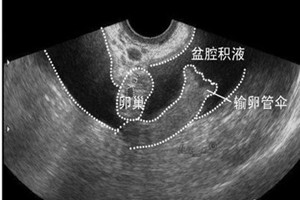

1、如果是因严炎症引发的盆腔积液,就会导致一系列的生殖器官炎症,但也有少数的盆腔积液是因宫外孕破裂、黄体破裂、盆腔脓肿等疾病引起。此外,因盆腔炎引起的积液最好做后穹隆穿刺检查,鉴定下液体的性质。

2、发现患有盆腔积液长期的得不到及时的治疗,就很容易引发致盆腔粘连、输卵管堵塞等,最终导致不孕,如果在平时出现下腹疼痛、腰骶酸痛、白带增多等症状时,就要考虑是慢性盆腔炎,需及时的进行治疗,以免炎症加重,增加积液的量。